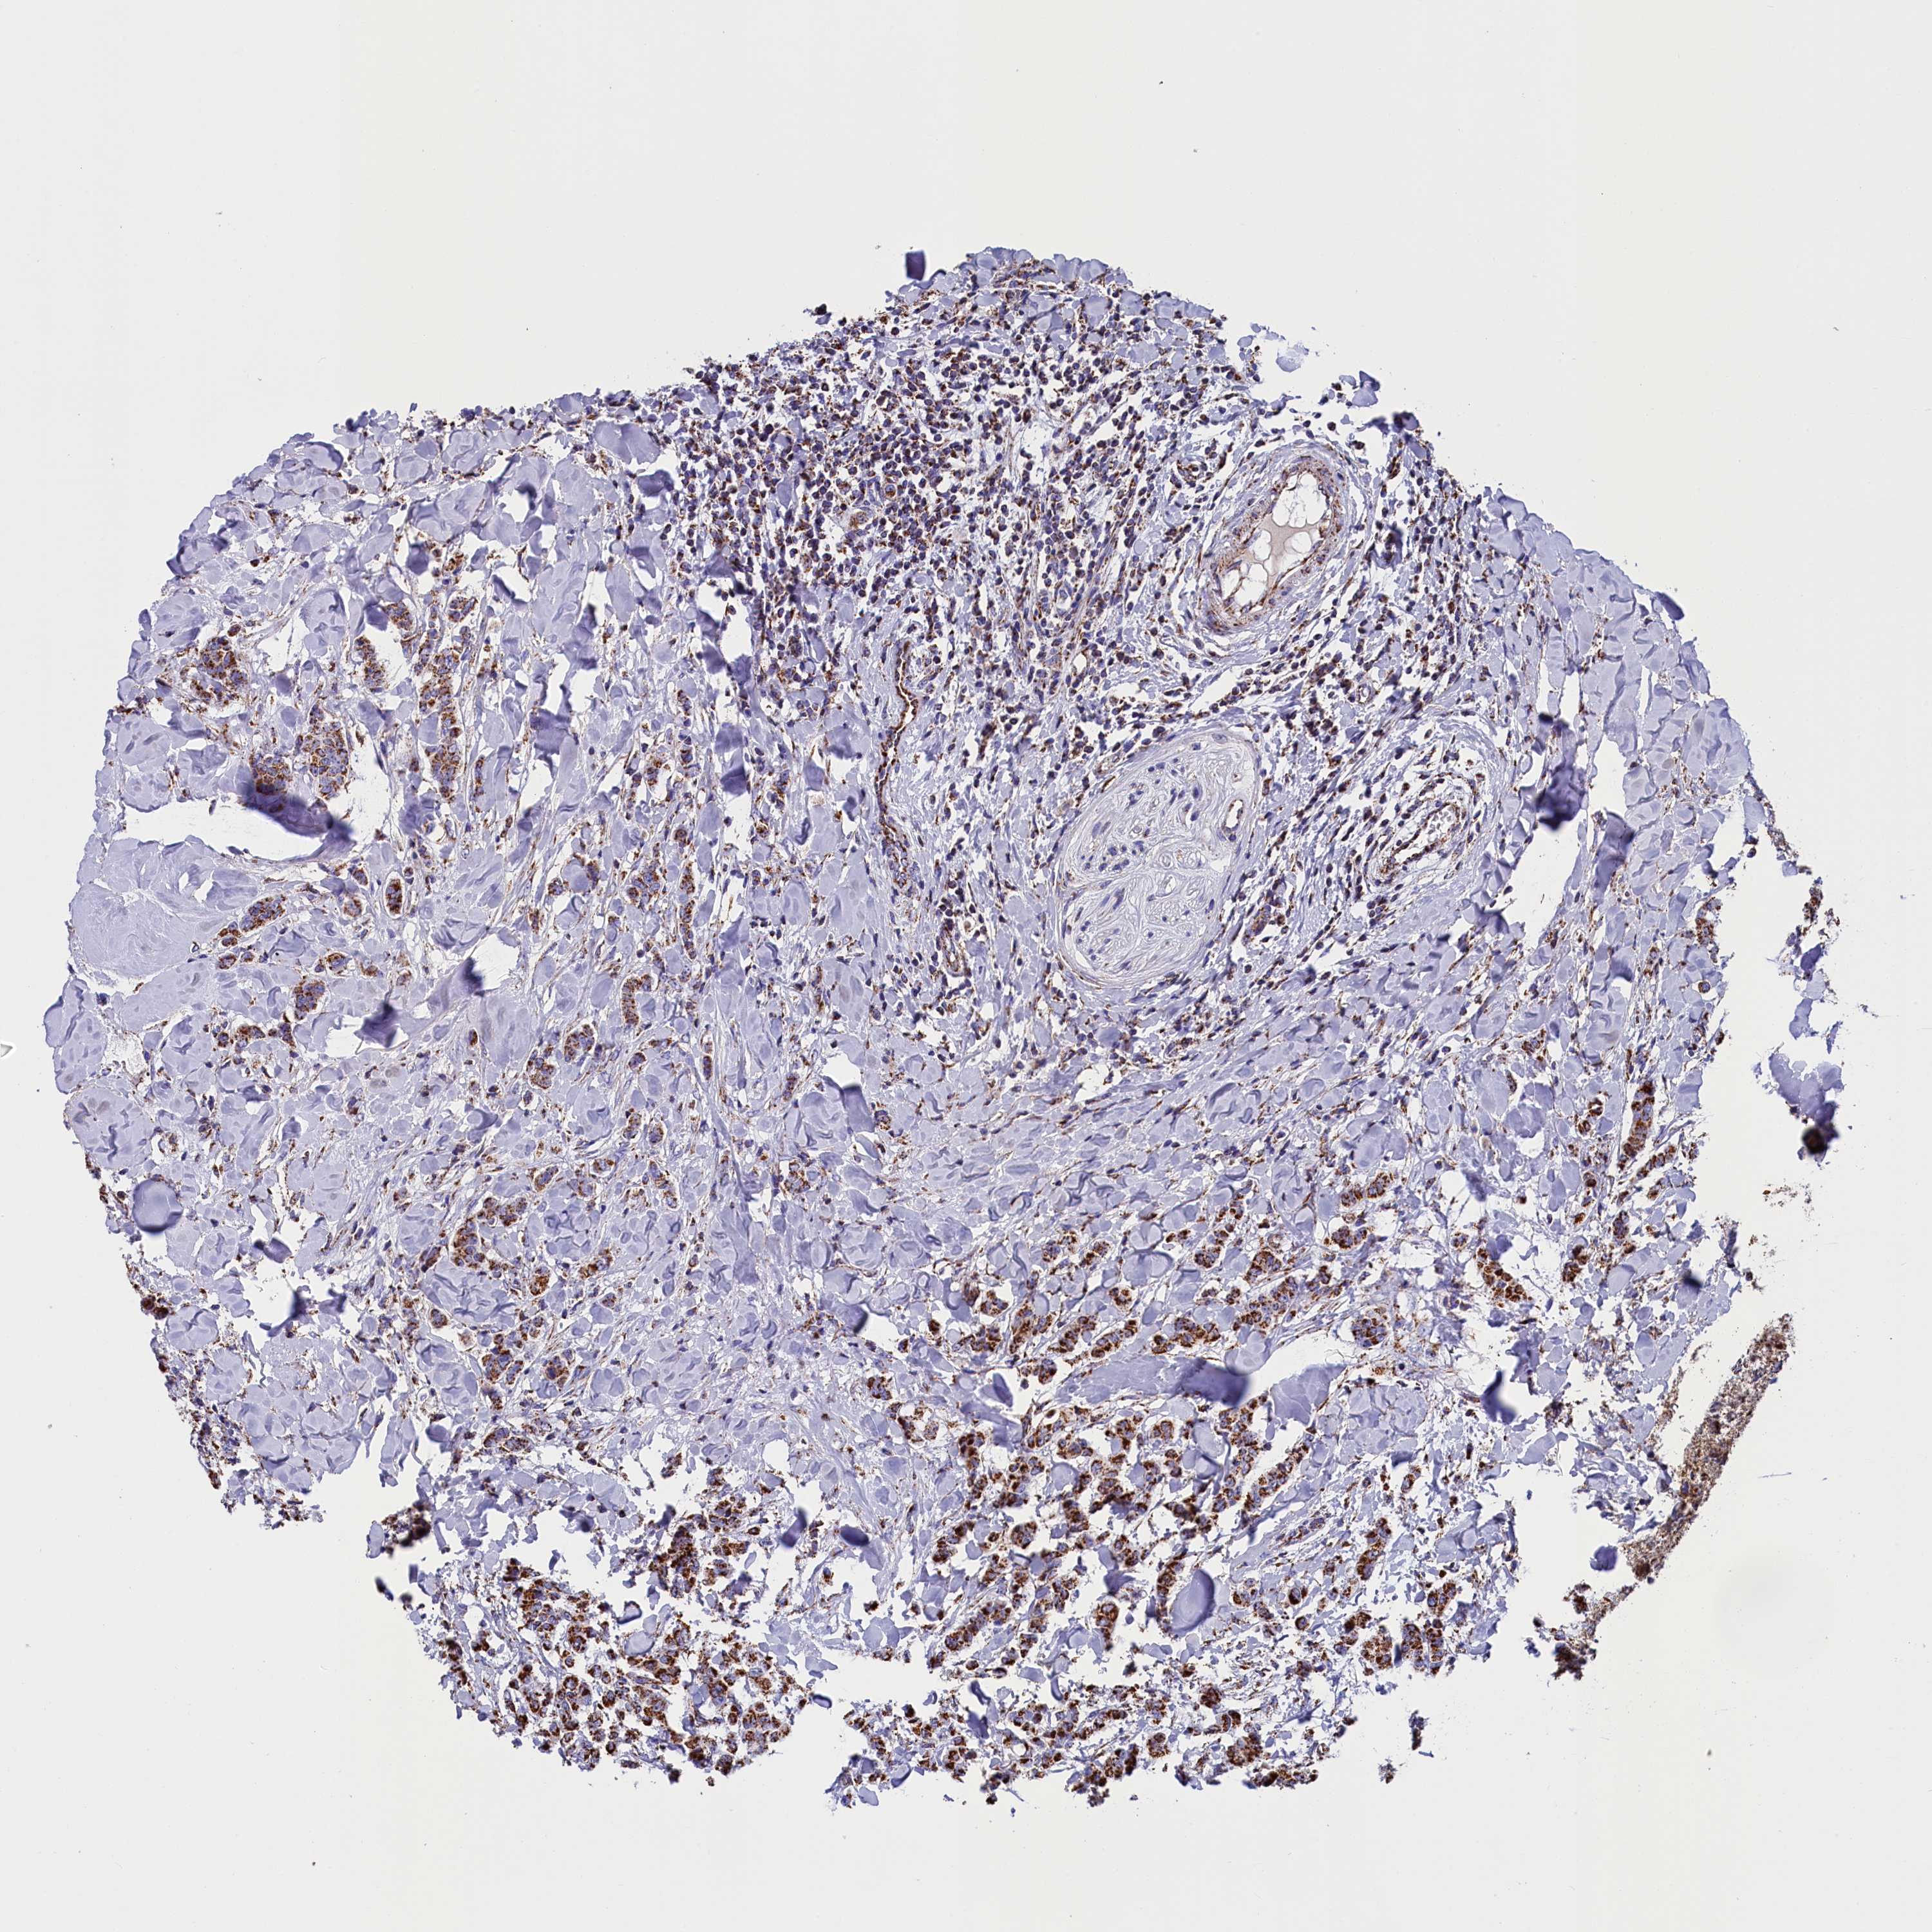

BRCA TCGA BRCA VALIDATION PROTEIN EXPRESSION

ANTIBODIES

AND

VALIDATION